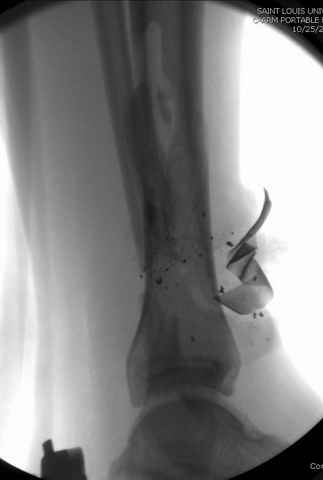

На снимках варианты фиксации малоберцовой:

№ 2-5 при огнестрельном переломе

DK> № 2-5 при огнестрельном переломе

Перелом оскольчатый с диастазом и нефиксация грозила бы ложным

суставом, здесь трудно не согласиться, но... осколок на место поставлен

не был... Вполне возможно, что все и сраслось, но... Никаких проблем в

данном конкретном случае не было? Болей там всяких, тендинитов etc?